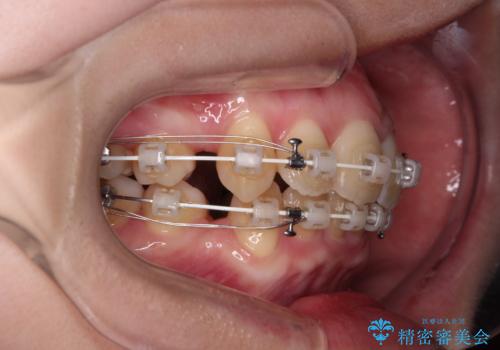

- 審美装置

上下左右第一小臼歯4本を抜歯して、積極的に口元を引っ込めるよう、ワイヤー装置にて矯正治療を行うこととしました。

口の閉じにくさが改善され、横顔のシルエットも大幅に改善されました。